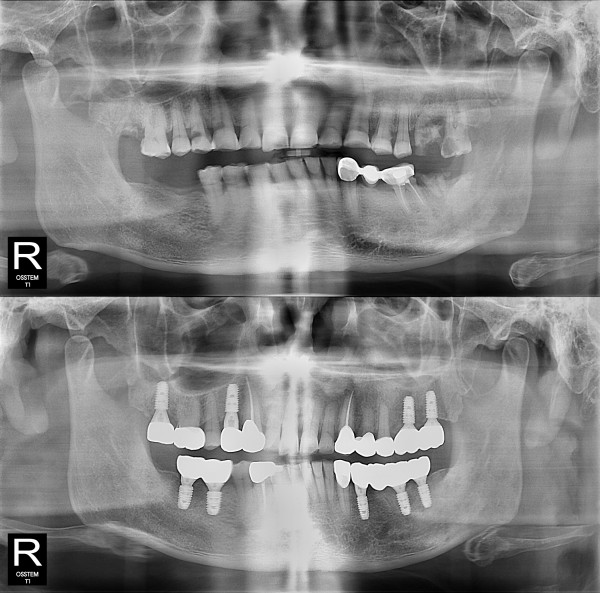

임플란트

부분 임플란트